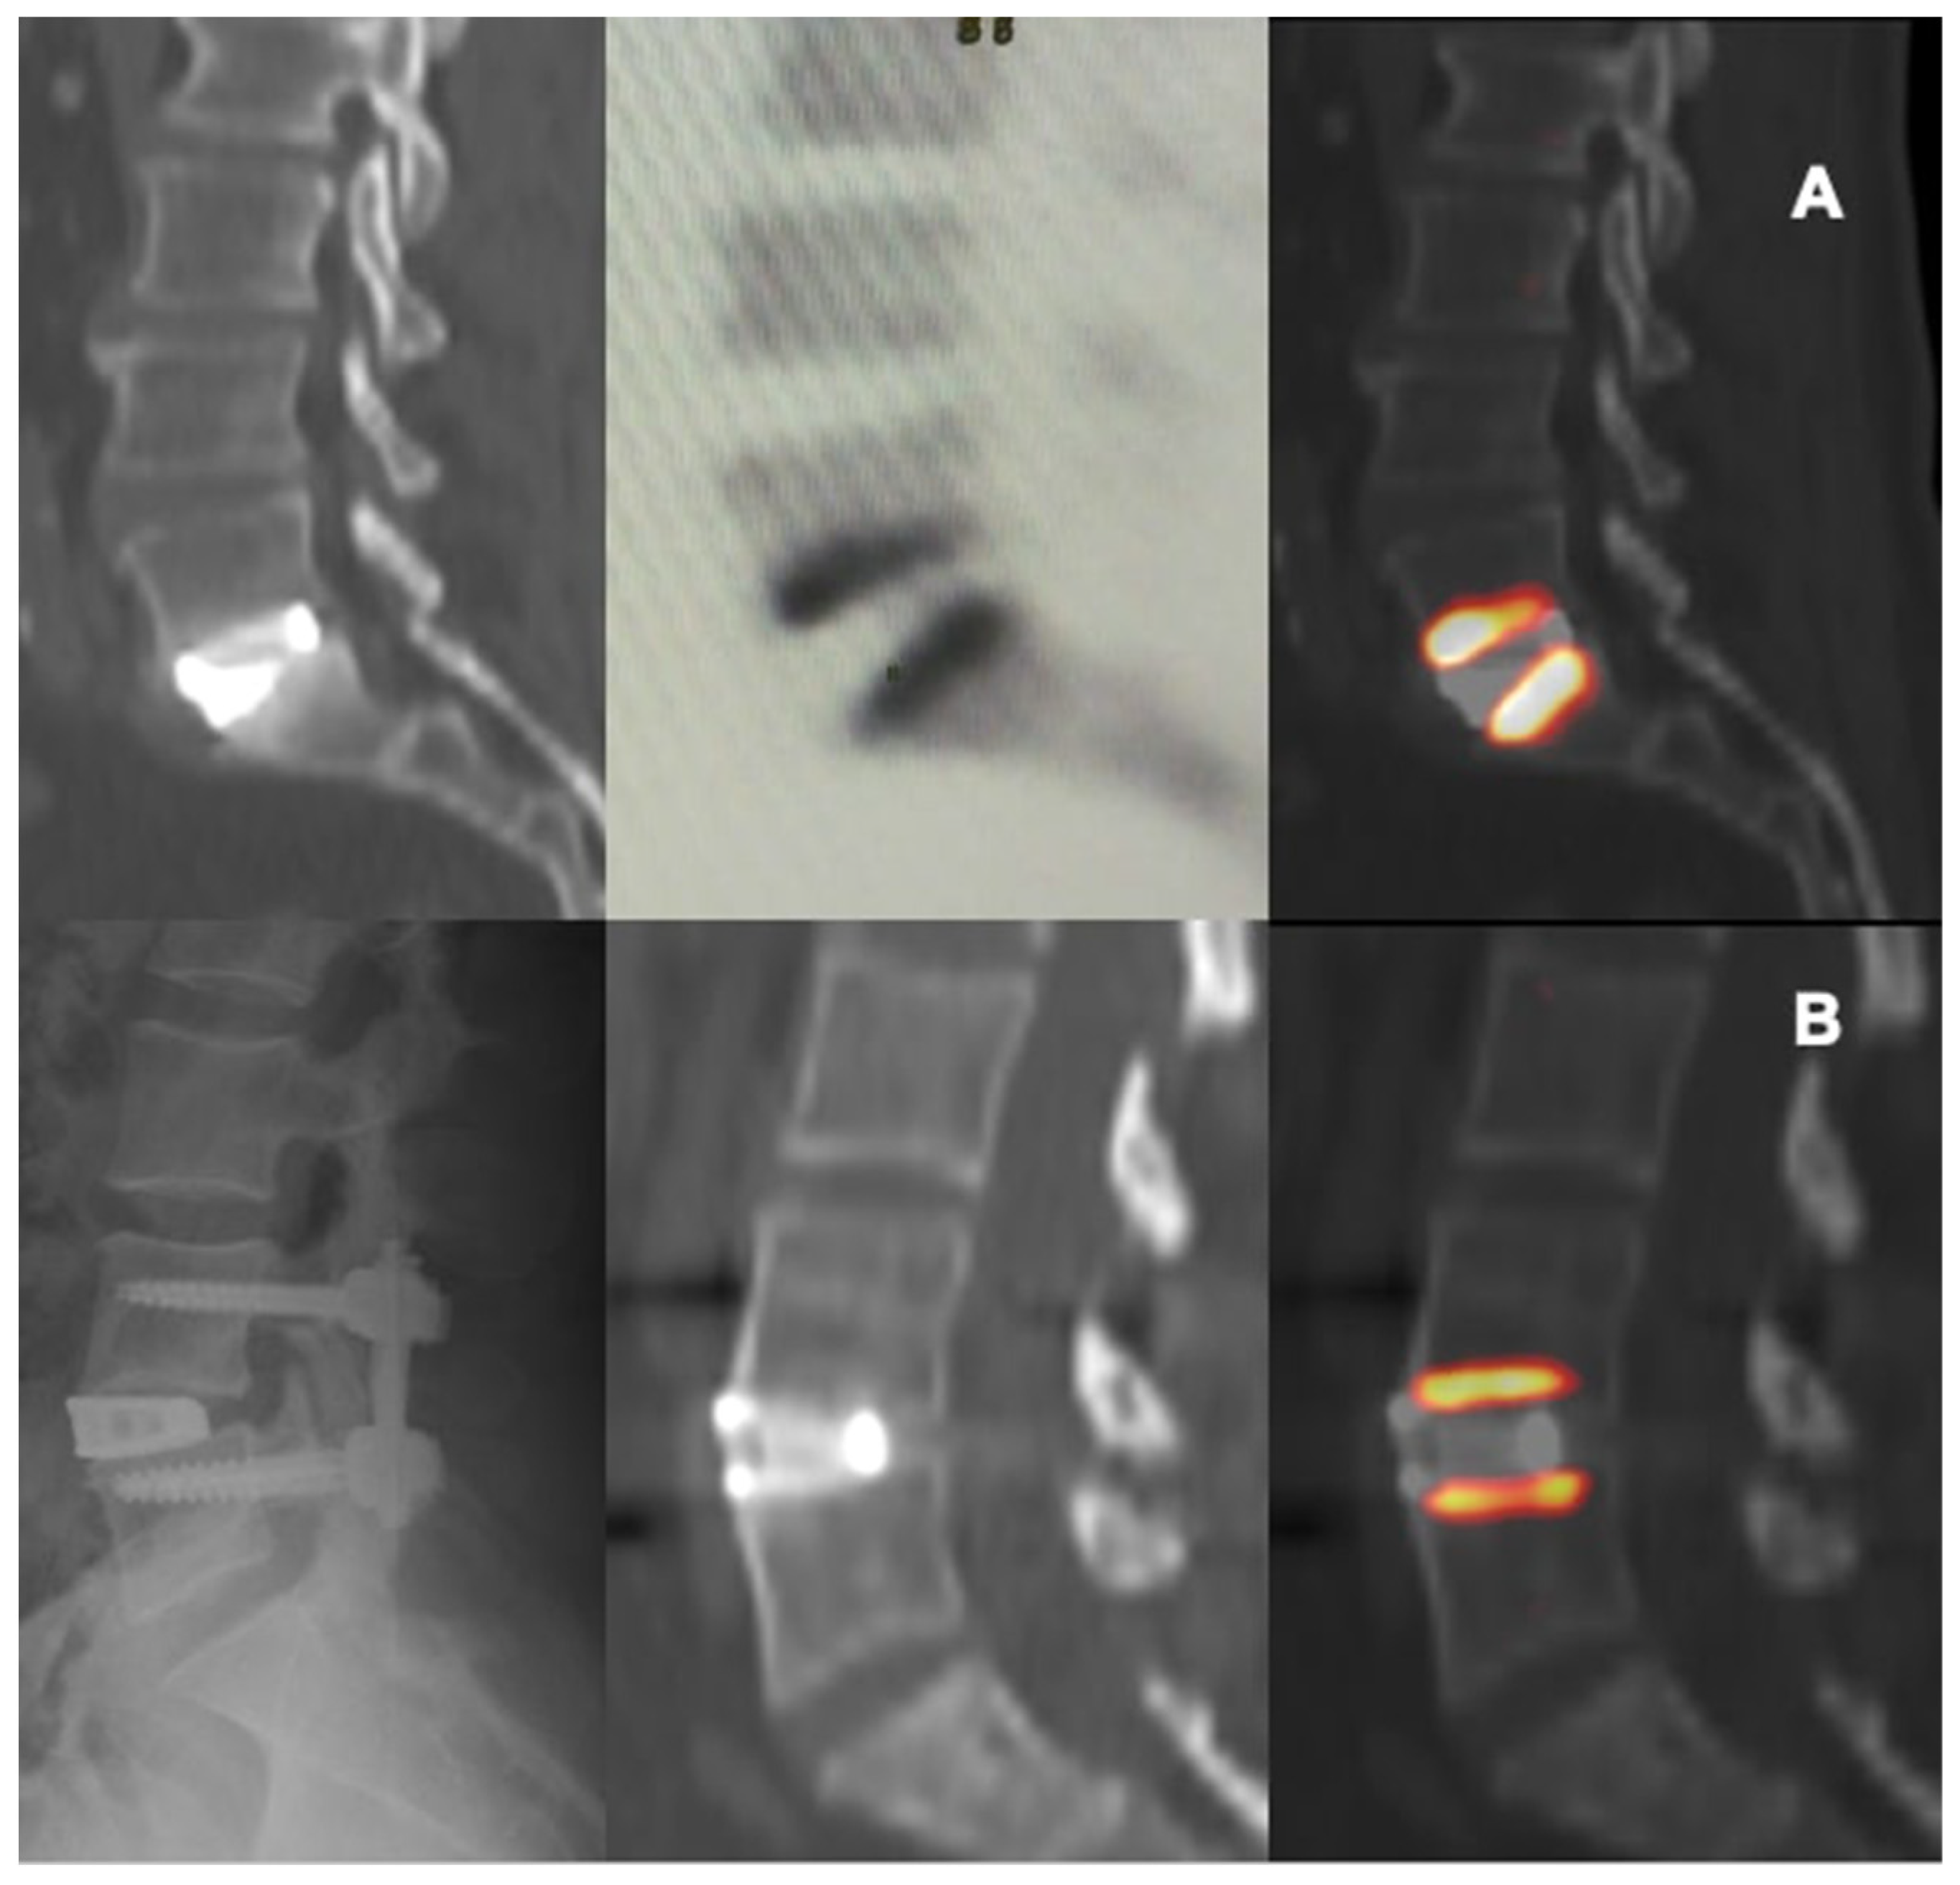

In this study the use of 18F-NaF PET/CT provided some adjunctive information about the metabolic-reparative reaction following the implantation of an interbody fusion cage during clinical follow-up; PET/CT supports the evidence regarding the ability of the cage to reach effective early osteo-integration.(Figure 4 and Figure 5) and provide some indications regarding the time required for the bone-remodeling process (the patients underwent PET examinations at different times and this has undoubtedly helped to give value to the final results).

Figure 4. CT and PET images showing metabolic activity on vertebral plates after arthrodesis surgery with trabecular titanium cage. L5-S1 ALIF, 11 weeks (A); L4-L5 XLIF, 27 weeks (B).

According to our results, tracer uptake was already visible in the first week after implantation. This first finding is probably related to the increase in blood flow after preparation of the vertebral endplate and to the consequent bone-cell activation at the contact surface. Therefore the metabolic activity, probably linked to the osteogenic activity, increases progressively until reaching a peak between approximately the 3rd and 4th month after surgery (Figure 2 and Figure 3). This progressive increase in activity can be correlated, as supported by in vitro studies, to the migration, adhesion, and growth of cells from the vertebral bone tissue and to consequent osteoblastic activity with apposition of the bone matrix within the cage pores [34]. In the later stages, the metabolic hyperactivity on the vertebral endplates decreases progressively and tends to disappears around the 10th–12th month after surgery (Figure 2 and Figure 3). This reduction may be the expression of a lower need for bone remodeling caused by sufficient acquired interbody fusion and stability [35,36]. The reparative phase could tend to run out after the formation of bone bridges between the cages and the vertebral plate. The growth of tissue inside the cage can be the basis for a real osteo-integration avoiding delayed subsidence and ensuring stability of the obtained correction.